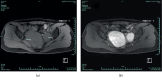

Leiomyomatosis Peritonealis Disseminata (LPD) is an uncommon disease characterized by presence of Multiple Leiomyomas in the abdominal and pelvic cavity. Increasingly, literature supports that LPD is an iatrogenic condition. Malignant transformation of LPD is rarely reported. We hereby report a case of a middle-aged female patient who was diagnosed with malignant sarcomatous degeneration in LPD. Gynecologists may get inspiration from this case report.